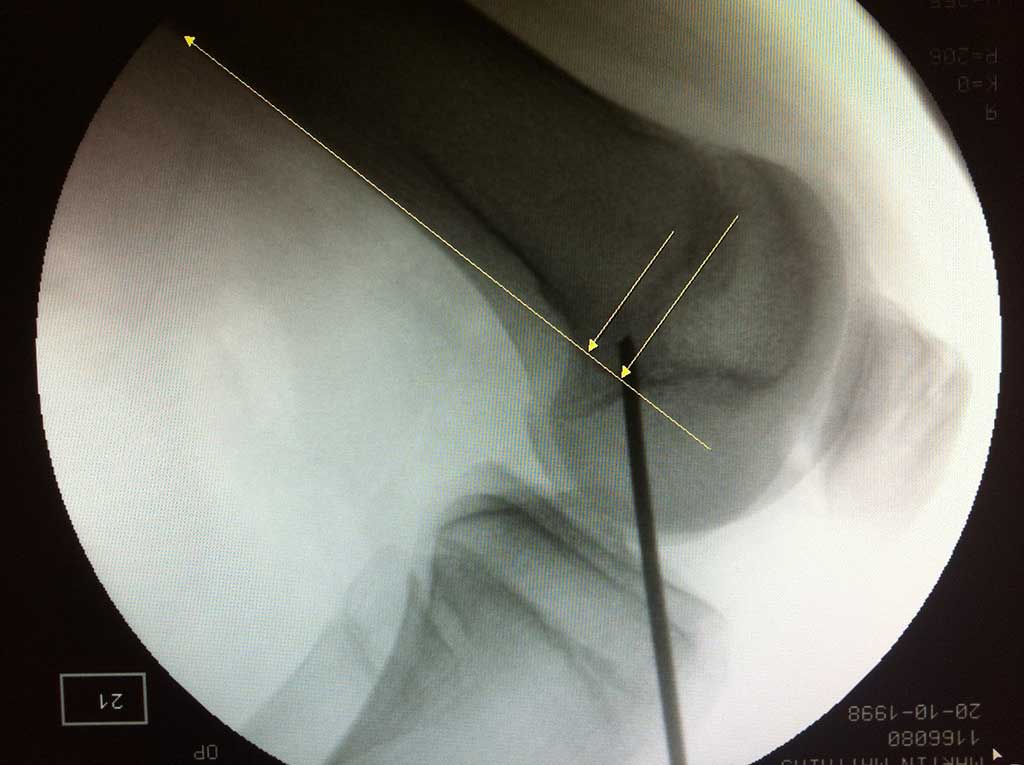

Arthroskopischer Kreuzbandersatz

Wie läuft die Operation ab ?

Eine Kreuzbandersatzplastik ist sehr elektive Operation, die ERST !!! dann durchgeführt werden soll, wenn sich das zu operierte Kniegelenk von dem Unfall " erholt " hat und möglichst abgeschwollen, schmerzfrei beweglich ist. Wird der Eingriff am immer noch deutlich gereizten Knie durchgeführt, ist es mit wesentlich längerer Nachbehandlungszeit, hartnäckigen Restbeschwerden und nicht selten Beweglichkeitseinschränkung

zu rechnen.

Diese arthroskopische Operation kann entweder ambulant oder stationär durchgeführt werden. Wir bieten beide Optionen an.

Man kann zwischen Vollnarkose und Spinalanästhesie wählen. Selbstverständlich werden auch alle anderen Verletzungen im Knie ( Meniskusriss, Knorpelschaden ) gleichzeitig mitbehandelt. Von mehreren Operationen wegen einer Knieverletzung ist intensiv abzuraten, trotzdem sieht man dies immer wieder!

Nach präziser arthroskopischer Anlage von zwei Bohrkanälen jeweils ein im Oberschenkelknochen und Schienbeinkopf, wird das VKB Transplantat aus einer oder zwei körpereigenen Sehnen ( Semitendinosus, Gracilis ) ins Kniegelenk eingezogen und in den Kanälen befestigt.

Die Op Dauer beträgt 30-45 Minuten, ggf. länger bei gleichzeitiger Versorgung von Begleitverletzungen.